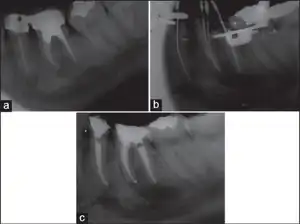

Dentistry

Paresthesia or "persistent anesthesia" is a transient or potentially permanent condition of extended numbness after administration of local anesthesia and the injected anesthetic has terminated.[15]

Potential causes include trauma introduced to the nerve sheath during administration of the injection, hemorrhage about the sheath, type of anesthetic used, or administration of anesthetic potentially contaminated with alcohol or sterilizing solutions.[16]